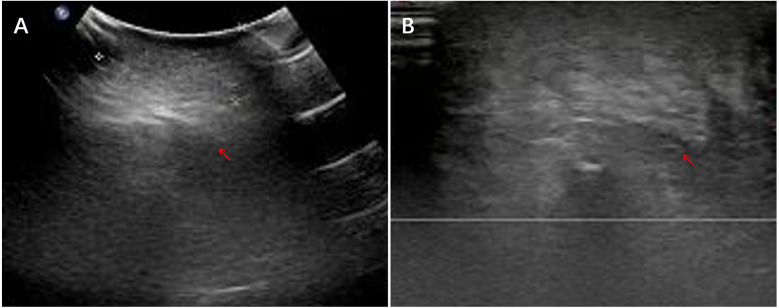

背景:炎性肌纤维母细胞瘤(IMT)是一种罕见的中间恶性潜能间充质肿瘤。虽然其临床病理特征已在成人中描述,但儿科人群的综合数据仍然有限。方法:回顾性分析2016年1月至2024年6月山西省儿童医院诊断为IMT的儿童患者。系统分析临床资料、影像学、组织病理学、免疫组化(IHC)和结果。结果:共纳入16例临床资料及随访资料完整的患者。男性10例,女性6例,中位年龄5.0岁。原发肿瘤部位及临床表现多样:8例位于腹腔及盆腔,表现为腹痛、恶心、呕吐、发热;4例位于头颈部及面部,3例表现为无痛性局部肿块,1例表现为吸气性呼吸困难;胸壁、臀区、左上肢各1例,均表现为无痛性局部肿块;肺部1例,表现为咳嗽、咳痰、反复呼吸道感染。所有16例患者均接受手术治疗;3例局部复发需要再次手术。最后随访中,15例无病,1例在alk靶向治疗下保持稳定。结论:儿童IMT是一种罕见的低级别恶性肿瘤,预后良好。完全手术切除仍然是治疗的基石。alk靶向治疗可使不可切除或复发性疾病的患者受益。由于有复发的危险,需要长期监测。

Results: A total of 16 patients with complete clinical data and follow-up information were included. There were 10 male and 6 female patients, with a median age of 5.0 years. The primary tumor locations and clinical manifestations were diverse: 8 cases were located in the abdominal and pelvic cavities, presenting with abdominal pain, nausea, vomiting, and fever; 4 cases were located in the head, neck, and facial region, with 3 presenting as painless localized masses and 1 with inspiratory dyspnea; 1 case each occurred in the chest wall, gluteal region, and left upper limb, all presenting with painless localized masses; and 1 case occurred in the lung, presenting with cough, sputum, and recurrent respiratory infections. All 16 patients underwent surgery; three developed local recurrence requiring re-operation. At last follow-up, 15 were disease-free and one remained stable on ALK-targeted therapy.